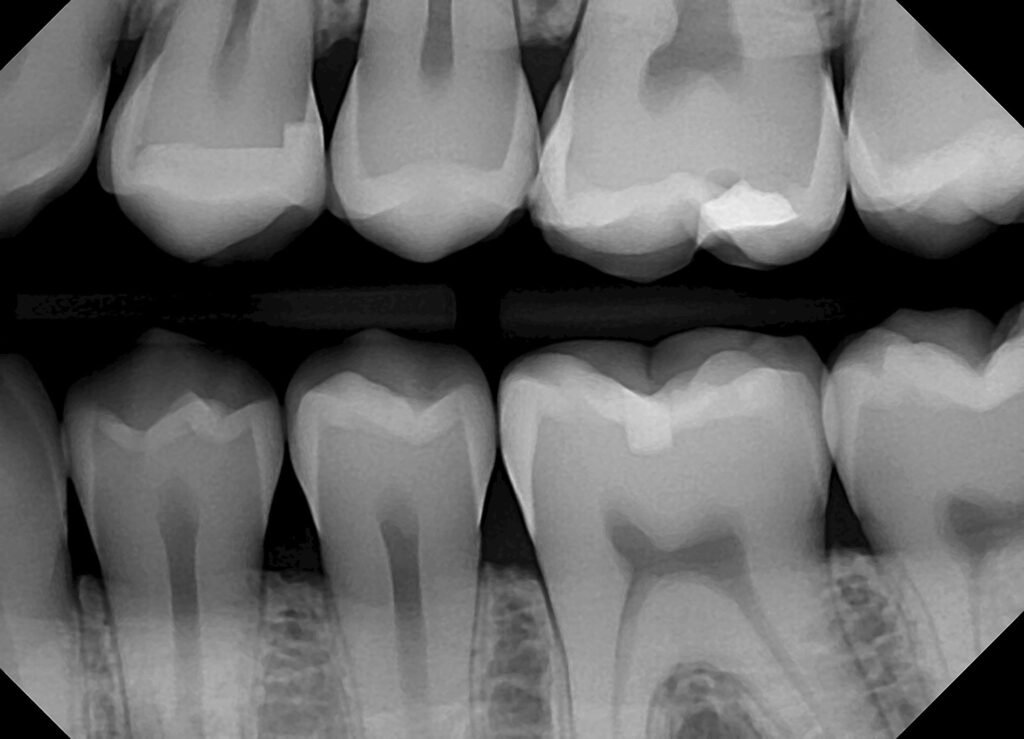

Bitewing X-Rays

Ideal for detecting cavities between teeth.